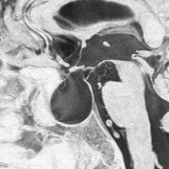

MRI画像(T1高信号のもの)

ラトケのう胞はT1強調画像で白く(左:高信号)にみえて,T2強調画像で黒く(右:低信号)にみえることもあります。前の例とはかなり違った印象です。中身は乳白色のドロドロの液体です。矢印のところは視神経交叉(左右の視神経がつながるところ)で,ラトケのう胞に圧迫されて弓形に変形しています。このくらいの視交差の変形では視野障害は出ませんし視力も低下しません。ですから,手術も何もしないで経過観察のみをします。多くの場合は,何も治療しなくて良いものです。この患者さんは無治療で経過を見ました。